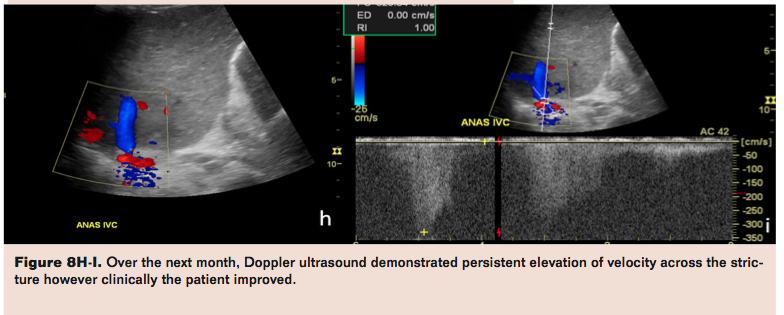

Hepatic Vein Stenosis

Hepatic vein stenosis (HVS) is a major post-transplant complication, especially in patients with partial liver graft transplantation producing graft failure with a reported incidence of 1% to 4%.5,27-29 Hepatic vein stenosis leads to hepatic congestion; manifestations include refractory ascites, refractory hydrothorax, and alteration of LFTs. Hepatic vein stenosis is most frequently seen at the site of the anastomosis and is less frequently seen in the hepatic vein itself. In the presence of clinical or radiologic suspicion of HVS, selective catheterization of all hepatic veins is necessary to confirm stenosis and to measure the trans-stenotic pressure gradient. Pressure gradients greater than 3 mmHg between the hepatic vein and the right atrium are considered pathological.29 For treatment of HVS, percutaneous interventions have adequate clinical and technical success rates. The initial treatment of choice is transjugular or transfemoral angioplasty or metallic stent placement.27-29 For example, in our case of hepatic venous stenosis, a 2-year-old who had previously undergone retransplantation benefitted from a dramatic reduction of the gradient from 15 mmHg to 4 mmHg, which was achieved with venoplasty (Figure 8). Multiple interventions may be required for long-term sustained patency, including the use of endovascular stent placement.30-32